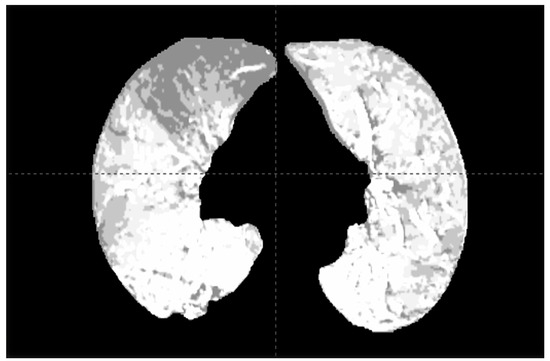

2.1. Dual-Energy CT and SPECT for Functional Lung Assessment

- Zhang, S.; Lapointe, A.; Simard, M.; Filion, M.P.; Campeau, D.; Roberge, H.; Bouchard, J.F.; Carrier, D.; Blais, S.; Bedwani, H. Bahig. (ABSTRACT) Evaluation of Radiation Dose Effect on Lung Function Using Iodine Maps Derived from Serial Dual-Energy Computed Tomograms. Int. J. Radiat. Oncol. Biol. Phys. 2020, 108, e366–e367. [Google Scholar]

- Zhang, S.; Simard, M.; Lapointe, A.; Filion, É.; Campeau, M.-P.; Vu, T.T.T.; Roberge, D.; Carrier, J.-F.; Blais, D.; Bedwani, S. Evaluation of radiation dose effect on lung function using iodine maps derived from dual-energy computed tomography. Int. J. Radiat. Oncol. Biol. Phys. 2024, 120, 894–903. [Google Scholar]